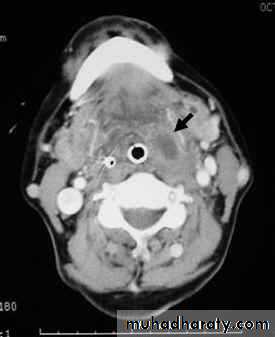

I.V. penicillin + Metronidazole. If the general condition is stable and airway is patent investigations can be done:

• WBC ↑, ESR ↑

• Needle aspiration will prove the diagnosis( if doubtful) and pus is send for culture.

• Orthopantomogram ( OPG) may shows root abscess.

• Ultrasound of the neck can differentiate between cellulites and abscess collection.

If there is no improvement within 24 hours abscess must be drained:

Under GA and ETT collar incision is done in the neck at the level of hyoid bone at the anterior border of sternomastoid muscle, pus is evacuated and drain is inserted